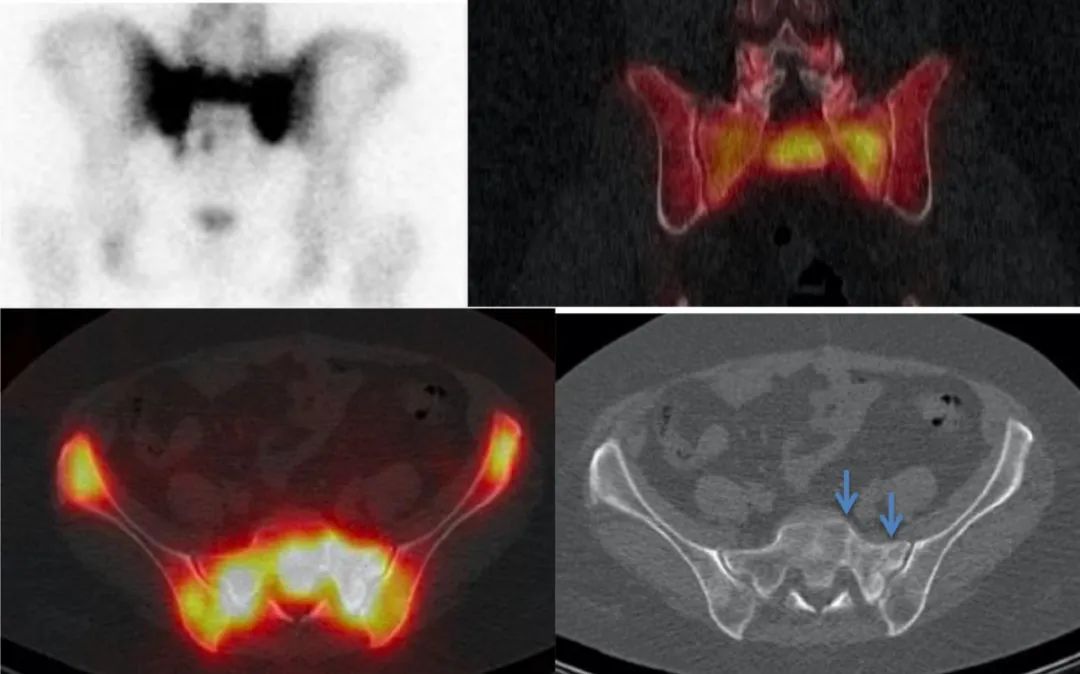

病例展示

患者女,79 岁,主诉骶尾部及左下肢疼痛近月余,无明确外伤史。外院 MRI 提示骶 1 椎体及左侧闭孔内肌异常信号,怀疑恶性肿瘤。既往无恶性肿瘤病史。为进一步明确骨病变性质行全身 18F-FDG PET/CT 显像,可见骶 1-2 椎体及骶 1-4 骶骨翼骨质不连续并见线样低密度影(骨折线),呈对称性 FDG 摄取显著增高,SUVmax 达 39.2,横向延伸至髂骨体,呈「H」形;另左侧耻骨体骨质不连续,见线样低密度影(骨折线),异常放射性浓聚。本例患者骶骨病变最大的特点为基本沿中线对称分布,骨质密度不均匀增高,占位效应不明显,FDG 摄取增高区呈特征性「H形 」分布。

基于骨病变代谢显著升高,对该患者来说,最重要的是除外恶性肿瘤(包括原发骨肿瘤和骨转移瘤),这也是患者做 PET/CT 的目的所在。若为骨转移瘤,PET/CT 未见原发恶性肿瘤征象,不支持;而原发骨肿瘤多呈溶骨性骨质破坏伴软组织肿块形成;以上改变均与本例患者影像表现不符。

有经验的影像医师应该会考虑到一个病:骶骨机能不全骨折,结合患者为绝经后老年女性(好发年龄),易有骨质疏松背景(危险因素),且左侧耻骨体骨折明确,因此考虑左侧耻骨体及骶 1-2 椎体、骶 1-4 骶骨翼均为机能不全骨折。